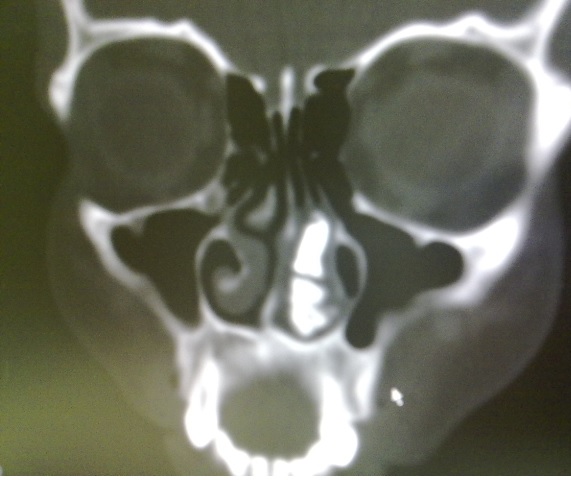

ADDRESS FOR CORRESPONDENCE Dr Jahangeer Ahmad Bhat, Senior Resident, Govt Medical College, Srinagar, India. Email: drjahangeerahmadbhat@yahoo.com Show affiliations A 15 year old female was referred from department of otolaryngology with a left sided nasal obstruction, headache, and epistaxis for the past 6 months. Intranasal examination revealed hard white mass surrounded by granulation tissue in left nasal cavity. Coronal CT scan was done using bone window setting which revealed a hyperdense vertically aligned mass lesion, two in number with attenuation equivalent to that of oral teeth. A slit-like cavity was noted within the mass. The mass was located in left nasal cavity between nasal septum and turbinate. Nasal mass was removed endoscopically and was subjected to microscopic examination which revealed mass composed of dentin with a layer of enamel covering it

Ectopic supernumerary teeth is a rare condition and there are multiple causes of ectopic eruption of teeth e.g., developmental disorders like cleft palate, facial trauma, maxillary infection, cyst, crowding, genetic factors and high bone density. {1,2} Ectopic teeth may be permanent, deciduous, and supernumerary. Imaging helps in making proper diagnosis and planning treatment. The incidence of supernumerary teeth is 0.1–1 percent in general population. {3} The most common location is the upper incisor area, known as mesiodens. The extra teeth have an atypical crown, and they may be in a vertical, horizontal, or inverted position. They may grow into the nasal cavity. The teeth may be asymptomatic or cause a variety of signs and symptoms, including facial pain, nasal obstruction, headache, epistaxis, foul-smelling rhinorrhea, external nasal deformities, and nasolacrimal duct obstruction. {4,5} Supernumerary teeth develop either from a third tooth bed that arises from the dental lamina near the permanent tooth bud or, possibly, from splitting of the permanent bud itself. {3} Another theory is that their development is a reversion to the dentition of extinct primates, which had three pairs of incisors. {3} The diagnosis of nasal teeth is made on the basis of clinical and radiographic findings. Clinically, an intranasal tooth may be seen as a white mass in the nasal cavity surrounded by granulation tissue and debris. {4} Radiographically, the nasal teeth in our patient appeared as radiopaque lesions with the same attenuation as that of the oral teeth. With the bone window setting, the central radiolucency, which is correlated with the pulp cavity, may have a spot or slit, depending on the orientation of the teeth. The soft tissue surrounding the radiopaque lesion is consistent with granulation tissue found on clinical and pathologic examinations. The differential diagnosis of nasal teeth includes radiopaque foreign body` rhinolith` inflammatory lesions due to syphilis, tuberculosis, or fungal infection with calcification` benign tumors, including hemangioma, osteoma, calcified polyps, enchondroma, and dermoid` and malignant tumors, such as chondrosarcoma and osteosarcoma. However, the CT findings of tooth-equivalent attenuation and a centrally located cavity are highly discriminating features that help to confirm the diagnosis. Removal of nasal teeth is generally advocated to alleviate the symptoms and prevent complications. |